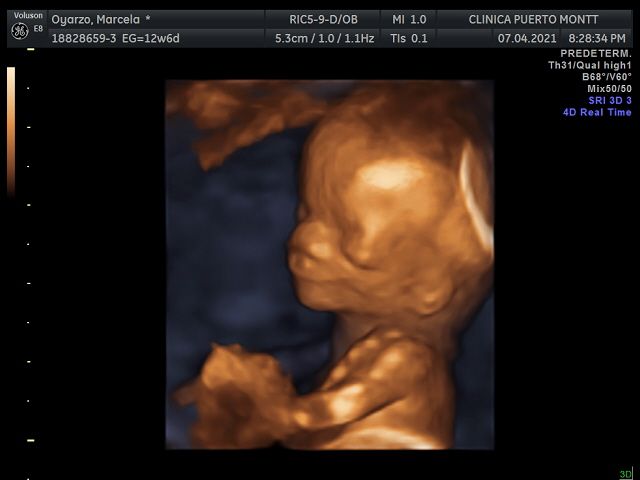

Ecografia Obstetrica y ginecologia

Ecografia Doppler obstetrica

Ecografia volumétrica (3 D y 4D)

Ecografía 4D 90000 $